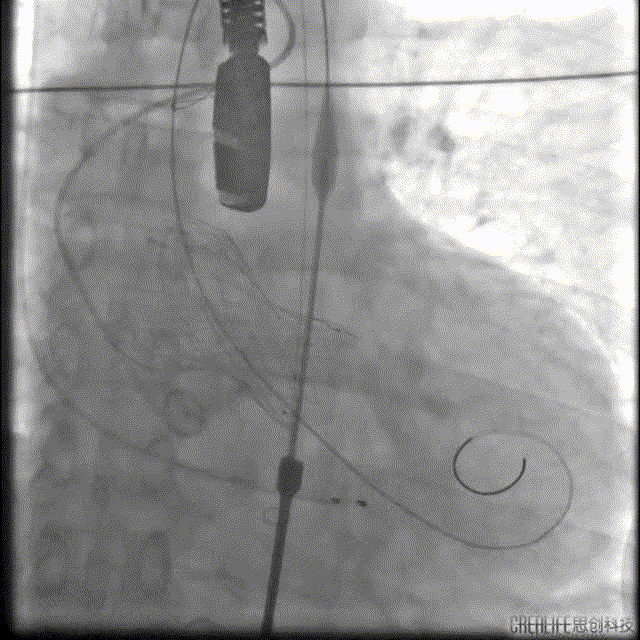

本例患者只有61岁,超声诊断低流速低压差AS,合并升主动脉扩张,CT下测量升主动脉超过50,原则上首选外科手术。但广东省人民医院大血管组会诊后考虑患者低流速低压差,行主动脉瓣和升主动脉置换术,手术风险极高,建议TAVR。从解剖上,瓣环流出道的大小分别是30、31,但瓣上结构是TYPE 0二叶瓣,重度钙化,联合部有钙化融合,瓣上短轴31,窦高度超过23,横位心,角度78°二叶瓣方向呈1点到7点方向。这种解剖做TAVR无疑挑战极大。对于低流速低压差的患者合并解剖挑战的病人,术前计划就是ecmo辅助下TAVR。考虑二叶瓣和重度钙化,目标瓣膜是29号,故用23号球囊预扩,尽量不破坏瓣上结构,另外考虑横位心,升主宽,破裂风险高,瓣膜跨瓣困难,故准备抓捕器辅助跨瓣。投照角度方面准备了瓣膜切线位(左肩),用来跨瓣和球扩,同时准备多一个右足位,这个角度下瓣环和人工瓣膜可以达到共平面,方便瓣膜定位。因为升主宽,横位心,主动脉迂曲,为减少破裂风险,没有选择plus。术中跨瓣遇到较大挑战,因为主动脉根部的角度大,普通的AL2,JR2,多功能导管均无法跨瓣,尝试直头导丝和弯头泥鳅也失败,最后是JL4加直头导丝成功跨瓣。预扩后瓣膜跨瓣尽管在抓捕器辅助下仍然非常困难,在反复尝试后侥幸跨瓣。瓣膜释放后位置偏深,但结合瓣膜角度,瓣周漏可以接受,压差消失,故未再行瓣中瓣。术中未发生停跳,故手术结束后撤去ECMO返回CCU。术后一个月随访EF值明显改善,患者自我感觉明显好转,虽然有中度瓣周漏,但是患者年轻,调整好心功能后,为以后外科置换升主动脉和主动脉瓣打下基础。

Nmued 23扩张

VenusA 29瓣膜定位